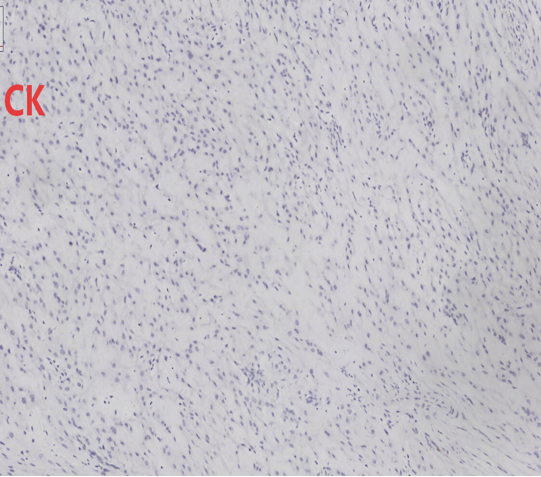

免疫组化结果:CK7(-)、CK5/6(-)、P63(-)、PAX-8(-)、Ki-67(+,约2%+)、INI-1(+,未突变)、SMA(+)、Des(+)、CD34(-)、S-100(-)、ER(+)、CK(-)、ALK(-)